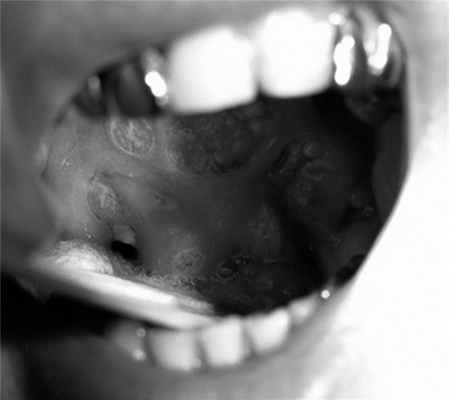

В беседе пациент предъявлял жалобы на чувство инородного тела в горле, гнусавость, выраженные боли в глотке, а также помеху при глотании пищи и жидкости. В анамнезе курение отрицал. При осмотре больного определялось опухолевое поражение ротоглотки, включая мягкое небо, с переходом за среднюю линию и на твердое небо, небную миндалину, дужки, стенку рото- и носоглотки. Просвет глотки был значительно сужен, а нижний полюс опухоли недостижим (рис. 1). Рис. 1. Картина распространения опухолевого процесса до начала лечения (описание в тексте). На шее с обеих сторон очаговой патологии не выявлено.

С 05.03.13 по 16.05.13 проведено одновременное химиолучевое лечение в разовой очаговой дозе (РОД) 2 Гр до СОД 70 Гр с цетуксимабом (стартовая доза 800 мг, далее 1 раз в неделю, поддерживающая доза 500 мг) (см. рис. 2). В процессе терапии имели место выраженные лучевые реакции в виде мукозита III степени RTOG, проявившиеся на ранних сроках (СОД 24 Гр), которые потребовали незапланированного перерыва в лечении в течение 14 календарных дней (СОД 40 Гр) (рис. 3). Рис. 3. Клиническая картина динамики мукозита в процессе лечения. Также отмечались характерные для таргетного препарата кожные реакции в виде папулезно-пустулезных высыпаний на коже лица, головы, груди, шеи, максимально выраженные до III степени через 2 дня после 4-го введения цетуксимаба, на фоне дерматита лица и шеи II степени в проекции полей облучения (рис. 4). Рис. 4. Клиническая картина динамики дерматита в процессе лечения. Пациенту проведены облучение в полном объеме, а также все запланированные введения цетуксимаба.